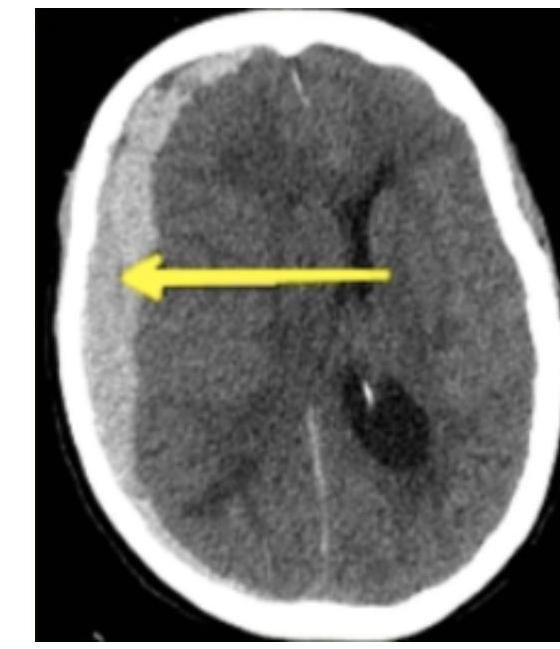

# TRAUMATISMO CRANEOENCEFÁLICO ## DEFINICIÓN Es una lesión directa en el cráneo, encéfalo o meninges por efecto mecánico provocado por un agente externo. Se clasifica en tres tipos: | TCE LEVE | Glasgow 14-15 | Cefalea leve, menos de 3 vómitos, sin pérdida de la conciencia | | :--------------: | :---------------------------------------------: | :----------------------------------------------------------------: | | TCE MODERADO | Glasgow 9-13 | Cefalea intensa, más de 3 vómitos, pérdida del estado de alerta, alteración de la conciencia, amnesia postraumática, convulsiones, sospecha de maltrato infantil, politraumatizado o trauma facial | | TCE GRAVE | Glasgow 8 o menor | Focalización, lesión penetrante del cráneo, fractura hundida o expuesta, disminución de Glasgow inicial, déficit neurológico de aparición posterior | **LESIÓN PRIMARIA**. Es el daño directo causado por el **impacto** del trauma o por los mecanismos de **aceleración-desaceleración**. Incluye **contusión cortical**, **laceración cerebral**, **fractura de cráneo**, **lesión axonal**, **contusión del tallo**, **desgarro dural o venoso**, etc. **LESIÓN SECUNDARIA**. Se desarrolla como consecuencia de la **injuria primaria**, desarrollando **sangrados**, **edemas**, **hiperemia**, **trombosis** y otros **procesos fisiopatológicos secundarios**. Incluye **hematoma intracraneano**, **epidural o subdural**, **edema cerebral**, **hipoxia y/o hipoperfusión cerebral**, elevación de **neurocitotoxinas** y **radicales libres**, **neuroinfección** y aumento de la **hipertensión endocraneana**. # EPIDEMIOLOGÍA - Es la causa más frecuente de coma (en ausencia de tumores o intoxicaciones). - Causa más frecuente de epilepsia en adolescentes y adultos jóvenes. ## FACTORES DE RIESGO - Causa y mecanismo de la lesión. - Tiempo transcurrido. - Estado mental subsecuente. - Presencia de crisis convulsivas postraumáticas. - Signos clínicos de fractura de cráneo. - Déficit neurológico específico. - Trastornos de la coagulación y uso de fármacos. - Sospecha de maltrato en menores de 18 años. ## ESCALA DE GLASGOW ADULTOS vs. NIÑOS | RESPUESTA OCULAR | | Puntos | | :---------------: | :--------------: | :------: | | **ADULTOS** | **LACTANTE** | | | Espontánea | Espontánea | 4 | | A estímulos verbales | A estímulos verbales | 3 | | Al dolor | Al dolor | 2 | | Ausencia de respuesta | Ausencia de respuesta | 1 | | RESPUESTA VERBAL | | | | **ADULTOS** | **LACTANTE** | | | Orientado | Sonríe, arrulla, gorgorea | 5 | | Desorientado / Confuso | Llora apropiadamente | 4 | | Palabras incoherentes | Grita, llanto inadecuado | 3 | | Sonidos incomprensibles | Quejido - gruñido | 2 | | Ausencia de respuesta | Sin respuesta | 1 | | RESPUESTA MOTORA | | | | **ADULTOS** | **LACTANTE** | | | Obedece órdenes | Adecuada al hablarle | 6 | | Localiza el dolor | Localiza el dolor | 5 | | Retira lo que le causa dolor | Retira lo que le causa dolor | 4 | | Flexión anormal | Flexión anormal | 3 | | Extensión anormal | Extensión anormal | 2 | | Ausencia de respuesta | Ausencia de respuesta | 1 | # MANEJO INICIAL DEL TCE ## TRAUMA LEVE (GLASGOW 14-15) Evaluación: Una vez documentado que se trata de un paciente con **TCE Leve**, se sabe que el riesgo de **complicaciones** es mínimo, por lo que el paciente no amerita **manejo intrahospitalario**. Monitorización: La **vigilancia** estará a cargo de los padres o **custodios** del menor en **DOMICILIO**. - La vigilancia de 6 horas en hospital es a criterio de decisión del médico. - No existe evidencia de que deba impedirse el **sueño** en las horas posteriores (incluso la falta de sueño puede modificar la conducta del paciente, dificultando la vigilancia de **datos de alarma**). - Se sugiere despertarlo cada 3 horas para evaluarlo. Indicaciones de una **NUEVA VALORACIÓN** (datos de alarma): - 3 o más vómitos en 24 horas. - Cefalea intensa. - Imposibilidad para establecer o mantener estado de despierto. - Crisis convulsivas. - Cambios en la conducta del menor. - Cualquier déficit neurológico (amaurosis, amnesia, paresia). - Presencia de hemorragia o salida de líquido por nariz u oído. - Marcha tambaleante o posturas anormales. TRAUMA MODERADO (GLASGOW 9-13) **VALORACIÓN E INVESTIGACIÓN EN URGENCIAS**: - **ABC**. - Deben ser valorados en un tiempo máximo de 15 minutos. - Si clínicamente se evidencia una lesión cerebral o de columna cervical, la valoración debe ser extensa. Criterios para realizar **RX**: - Menores de 1 año. - Sospecha de maltrato (complementar con huesos largos). - Pérdida de conciencia superior a cinco minutos (solo si no hay TAC). - Crepitaciones o hundimiento. - Trauma facial grave. - Rx Cervical indicada si hay politraumatismo, TCE Grave, dolor cervical (proyección antero-posterior). - No deben ser usadas como diagnóstico, solo de apoyo. # CRITERIOS PARA TAC INMEDIATA - Pérdida de conciencia de más de 5 minutos. - Amnesia anterógrada o retrógrada de más de 5 minutos. - Letargia. - 3 o más vómitos. - Convulsiones postraumáticas (sin antecedente de epilepsia). - Glasgow <15 en menores de 1 año y Glasgow <14 en el resto de pediátricos. - Sospecha de lesión abierta o deprimida (fontanela tensa). - Cualquier signo de fractura de base del cráneo. - Déficit neurológico focal. - Si es menor de un año: hematoma, edema, laceración de +5 cm en cabeza. - Mecanismo peligroso: accidente de alta velocidad, caída mayor a 3 metros, daño de alta velocidad con proyectil. - Coagulopatía (antecedente de sangrado o anticoagulantes). ## CRITERIOS PARA RMN: - No se indica como método primario de investigación para lesión cerebral secundaria a TCE. - Puede otorgar información adicional para el pronóstico (detecta lesiones pequeñas que no se ven en TAC). ## CRITERIOS PARA INTUBACIÓN EN TCE PEDIÁTRICO: - Escala de coma de Glasgow menor a 10 (adultos < 8). - Disminución de Glasgow de +3 puntos posterior a una calificación inicial. - Coma. - Anisocoria > 1 mm. - Lesión cervical espinal que comprometa ventilación. - Apnea. - Pérdida de reflejos de protección laríngea. - Hipercapnia (PaCO2 > 45 mmHg) o Hipoxemia (PaO2 < 60 mmHg). - Hiperventilación espontánea que ocasione PaCO2 < 25 mmHg. ## ESTABILIZACIÓN CIRCULATORIA - Determinación de FC, TA, calidad de pulsos centrales, periféricos y llenado capilar. - **Reanimación agresiva con fluidos** es necesaria si hay hipotensión. - - **CRISTALOIDES ISOTÓNICOS** 20 ml/kg (Cloruro de Sodio 0.9%). ○ No usar hipotónicos (Solución glucosada o Agua Inyectable) para reanimación inicial. - La TA mínima (percentil 5) para niños se obtiene = **70 + (Edad en Años x 2)**. - No se recomienda usar diuréticos. # HEMATOMA EPIDURAL - Consiste en la **acumulación de sangre** entre el **cráneo y la duramadre**. - Representa el 2-4 % de los traumas que requieren hospitalización. - Es más común en **niños, jóvenes y adultos jóvenes** (entre más edad, la **duramadre** está más pegada al hueso). ## ETIOLOGÍA 1. **SANGRADO ARTERIAL** (75-95% asociado a **fracturas**) → 70 % región **TEMPORAL**. a. **ARTERIA MENÍNGEA MEDIA**. 2. **Sangrado Venoso** (15%). ## CLÍNICA 1. **Pérdida de conciencia y luego periodo lúcido**, posterior **deterioro neurológico** (50 % de los casos). 2. Cefalea, vómito, hemiparesia, deterioro de alerta. 3. **Coma**. 4. **Herniación**. 5. **Muerte**. **TRIADA DE CUSHING** (Hipertensión Intracraneana) Sucede cuando el **efecto de masa** aumenta la **PIC**: **Hipertensión** + **Bradicardia** + **Alteraciones Respiratorias**. ## DIAGNÓSTICO **TOMOGRAFÍA COMPUTARIZADA**: Hallazgos: Forma de **LENTE BICONVEXA** + (puede) **Desplazamiento de línea media** (en los exámenes lo pueden mencionar como forma de **naranja o limón**). ## TRATAMIENTO ## QUIRÚRGICO:  El paciente puede estar asintomático; el **tratamiento quirúrgico** será en los que el **desplazamiento de la línea media** sea **significativo** (**efecto de masa > 10 mm**). **CIRUGÍA - CRANEOTOMÍA + DRENAJE DE HEMATOMA** (se realiza **evacuación y hemostasia**). Si hay **Hipertensión Intracraneana** - **Manitol al 20 %**. ## PRONÓSTICO La **Mortalidad** es del **5%**. - Si se presenta en región **TEMPORAL** es **más peligroso** que el parietal debido al riesgo de **herniación** (puede empujar el lóbulo temporal y formar una **hernia uncal**). # HEMATOMA SUBDURAL - Originado por una **LESIÓN EN PLEXOS VENOSOS SUBDURALES Y VENAS PUENTE** que comunican hacia los senos venosos durales, es decir, **debajo de la duramadre** y **antes de la aracnoides**. Es **más frecuente en la población adulta mayor** (poco común en niños). **Localización más frecuente** - **Fronto-Temporal**. ## ETIOLOGÍA 1. **Contusiones cerebrales** (50%). 2. **Hemorragia subaracnoidea** (25%). La causa más común son las **caídas desde su propia altura**. 3. **Hematomas epidurales** (10%). ## FISIOPATOLOGÍA 1. **Acumulación de sangre** alrededor de **laceración del parénquima**. 2. **RUPTURA DE VENAS PUENTE** por **mecanismo de aceleración-desaceleración**. 3. **Lesión arterial** - **MUY RARO** (puede ser por **ruptura de aneurisma**). ## CLASIFICACIÓN - Agudo: 1-3 días (TAC Hiperdensa). - Subagudo: 4-14 días (TAC Isodensa). - Crónico: +15 días (TAC Hipodensa). ## CLÍNICA - **Dolor de cabeza**. - **Cambios en el estado mental**. - **Hemiparesia contralateral**. - **Focalización neurológica**. - **Pseudodemencia en ancianos**. # DIAGNÓSTICO ## Tomografía Computarizada ## Hallazgos: - Imagen en **Semiluna (Falciforme)** que sigue el contorno del cerebro. - (En los exámenes lo pueden mencionar como **banana**). ## TRATAMIENTO  QUIRÚRGICO: - Se realiza una **evacuación del hematoma + lavado + hemostasia + drenaje subgaleal**. ## PRONÓSTICO ## MAL PRONÓSTICO - **Hipotensión arterial**. - **Mayores de 60 años**. - **Glasgow menor a 6**. **MORTALIDAD** 50%. - **Hematomas de > 10 mm de espesor**. - **Desviación línea media mayor a 5 mm**. # EPIDURAL vs. SUBDURAL  EPIDURAL SUBDURAL # FRACTURA DE LA BASE DEL CRÁNEO Es importante evaluar las **fracturas craneales** ya que son **marcadores de intensidad** y **sugieren lesión intracraneal**. Las fracturas que presenten **fragmentos de hueso deprimido** necesitarán **reparación quirúrgica**. ## CLÍNICA - **Hemotímpano**. - Lesión de **PC** (Anosmia, PCI Frontoetmoidales, PC VII yd VIII por fracturas del peñasco y del VI par en las fracturas del clivus). - **Otorrea**. - **Epistaxis**.  | BASE ANTERIOR | **Equimosis periorbitaria (Ojos de Mapache)** y **Rinorraquia** | | :-------------: | :------------------------------------------------------------ | | BASE MEDIA | **Equimosis retroauricular (Signo de Battle)** y **Otorraquia** | | BASE POSTERIOR | Cuadro clínico no definido, se visualiza por **TAC** | ## DIAGNÓSTICO ## TOMOGRAFÍA COMPUTARIZADA - Se debe realizar en **TCE Moderado y Severo** para descartar lesiones. ## TRATAMIENTO - Conservador. # CONMOCIÓN CEREBRAL ## CLÍNICA - **Alteración del nivel de conciencia transitoria y duración variable**. - **Amnesia del episodio**. - **Incoordinación**. ## DIAGNÓSTICO - **TAC sin alteración radiológica**. ## TRATAMIENTO No precisa tratamiento específico. ## CONTUSIÓN CEREBRAL Corresponde al 9% de los TCE, por **mecanismos de golpe y contragolpe** (pueden ser **hemorrágicos o no**). ## CLÍNICA - Variable y limitado deterioro del estado neurológico. - Su comportamiento es **amenazante entre el día 4 y 7** debido al **efecto de masa** por la **contusión y el edema** con pico. ## DIAGNÓSTICO - **TAC** que evidencia **lesiones intraparenquimatosas hiperdensas pequeñas**. ## TRATAMIENTO - **Cirugía** dependiendo de la localización, tamaño y el estado neurológico del paciente. - **Anticonvulsivante profiláctico**. # LESIÓN AXONAL DIFUSA Traduce la suma de un concepto clínico (**coma traumático prolongado**) y un concepto anatomopatológico (**alteración del citoesqueleto**, con **degeneración del axón** y **desconexión del mismo o axotomía**). Tras el **TCE**, la **secuencia fisiopatogénica** sería una **primitiva excitación neuronal** seguida de una **inhibición**, produciéndose la **pérdida de conciencia** y la **liberación masiva de iones al medio extracelular**. ## CLÍNICA **Deterioro precoz y mantenido del nivel de conciencia**. ## DIAGNÓSTICO - **TAC de aspecto aparentemente normal**. ## TRATAMIENTO **Conservador**.  # MANEJO TCE NIÑOS  # EVALUACIÓN INICIAL TCE ADULTOS  # MANEJO TCE ADULTOS  # MÉTODOS DIAGNÓSTICOS ADULTOS

# TRAUMATISMO CRANEOENCEFÁLICO ## DEFINICIÓN Es una lesión directa en el cráneo, encéfalo o meninges por efecto mecánico provocado por un agente externo. Se clasifica en tres tipos: | TCE LEVE | Glasgow 15- 14 | Cefalea Leve Menos de 3 vómitos Sin pérdida de la conciencia | | :--: | :--: | :--: | | TCE MODERADO | Glasgow 13 - 9 | Cefalea intensa Más de 3 vómitos Pérdida del estado de alerta Alteración de la conciencia Amnesia post-traumática Convulsiones Sospecha de maltrato infantil Politraumatizado o trauma facial | | TCE GRAVE | Glasgow 8 o menor | Focalización Lesión penetrante del cráneo Fractura hundida o expuesta Disminución de Glasgow inicial Déficit neurológico de aparición posterior | LESIÓN PRIMARIA. Es el daño directo causado por el impacto del trauma o por los mecanismos de aceleracióndesaceleración. Incluye contusión cortical, laceración cerebral, fractura de cráneo, lesión axonal, contusión del tallo, desgarro dural o venoso, etc. LESIÓN SECUNDARIA. Se desarrolla como consecuencia de la injuria primaria, desarrollando sangrados, edemas, hiperemia, trombosis y otros procesos fisiopatológicos secundarios. Incluye hematoma intracraneano, epidural o subdural, edema cerebral, hipoxia y/o hipoperfusión cerebral, elevación de neurocitotoxinas y radicales libres, neuroinfección y aumento de la hipertensión endocraneana # EPIDEMIOLOGÍA - Es la causa más frecuente de coma (en ausencia de tumores u ocupacional) - Causa más frecuente de epilepsia en adolescentes y adultos jóvenes. ## FACTORES DE RIESGO - Causa y mecanismo de la lesión - Tiempo transcurrido - Estado mental subsecuente - Presencia de crisis convulsivas postraumáticas - Signos clínicos de fractura de cráneo - Déficit neurológico específico - Trastornos de la coagulación y uso de fármacos - Sospecha de maltrato en menores de 18 años ## ESCALA DE GLASGOW ADULTOS V NIÑOS | RESPUESTA OCULAR | | Puntos | | :--: | :--: | :--: | | ADULTOS | LACTANTE | | | Espontánea | Espontánea | 4 | | A estímulos Verbales | A estímulos Verbales | 3 | | Al dolor | Al dolor | 2 | | Ausencia de respuesta | Ausencia de respuesta | 1 | | RESPUESTA VERBAL | | | | ADULTOS | LACTANTE | | | Orientado | Sonríe, arrulla, gorgorea | 5 | | Desorientado / Confuso | Llora apropiadamente | 4 | | Palabras Incoherentes | Grita, llanto inadecuado | 3 | | Sonidos Incomprensibles | Quejido - gruñido | 2 | | Ausencia de Respuesta | Sin respuesta | 1 | | RESPUESTA MOTORA | | | | ADULTOS | LACTANTE | | | Obedece órdenes | Adecuada al hablarle | 6 | | Localiza el dolor | Localiza el dolor | 5 | | Retira lo que le causa dolor | Retira lo que le causa dolor | 4 | | Flexión Anormal | Flexión Anormal | 3 | | Extensión Anormal | Extensión Anormal | 2 | | Ausencia de respuesta | Ausencia de respuesta | 1 | # MANEJO INICIAL DEL TCE ## TRAUMA LEVE (GLASGOW 14-15) Evaluación: una vez documentado que se trata de un paciente con TCE Leve, se sabe que el riesgo de complicaciones es mínimo por lo que el paciente no amerita manejo intrahospitalario. Monitorización: vigilancia estará a cargo de los padres o custidos del menor en DOMICILIO. - La vigilancia de 6 horas en hospital es a criterio de decisión del médico - No existe evidencia de que deba impedirse el sueño en las horas posteriores (incluso la falta de sueño puede modificar la conducta del paciente, dificultando la vigilancia de datos de alarma) - Se sugiere despertarlo cada 3 horas horas para evaluarlo Indicaciones de una NUEVA VALORACIÓN (datos de alarma) - 3 o más vómitos en 24 horas - Cefalea intensa - Imposibilidad para establecer o mantener estado de despierto - Crisis convulsivas - Cambios en la conducta del menor - Cualquier déficit neurológico (amaurosis, amnesia, paresia) - Presencia de hemorragia o salida de líquido por nariz.u oído - Marcha fambaleante o posturas anormales. TRAUMA MODERADO (GLASGOW 9 - 13) VALORACIÓN E INVESTIGACIÓN EN URGENCIAS: ## - ABC - Deben ser valorados en un tiempo máximo de 15 minutos - Si clínicamente se evidencia una lesión cerebral o de columna cervica, la valoración debe ser extesna, Criterios para realizar RX - Menores de 1 año - Sospecha de maltrato (complementar con huesos largos) - Pérdida de conciencia superir a cinco minutos (solo si no hay TAC) - Crepitaciones o hundimiento - Trauma facial grave - Rx Cervical indicada si hay lesiones politrauma, TCE Grave, dolor cervical (proyección antero-posterior - No deben ser usadas como diagnóstico, solo de apoyo. # CRITERIOS PARA TAC INMEDIATA - Pérdida de conciencia de +5 minutos - Amnesia anterógrada o retrógrada de +5 minutos - Letargia \Rightarrow 3 o más vómitos - Convusliones post traumáticas (Sin antecedente de epilepsia) - Glasgow <15 en menores de 1 año y Glasgow <14 en el resto de pediátricos - Sospecha de lesión abierta o deprimida (fontanela tensa) - Cualquier signo de fractura de base del cráneo - Déficit neurológico focal - Si es menor de un año: hematoma, edema, laceración de +5 cm en cabeza - Mecanismo peligroso: accidente alta velocidad, caída mayor a 3 metros, daño de alta velocidad con proyectil - Coagulopatía (antecedente de sangrado o anticoagulantes) ## CRITERIOS PARA RMN: - No se indica como método primario de investigación para lesión cerebral secundaria a TCE - Puede otorgar información adicional para el pronóstico (detecta lesiones pequeñas que no se ven en TAC) ## CRITERIOS PARA INTUBACIÓN EN TCE PEDIÁTRICO: - Escala de coma de Glasgow menor a 10 (adultos 8) - Disminución de Glasgow de +3 puntos posterior a una calificación incial - Coma - Anisocoria +1 mm - Lesión cervical espinal que comprometa ventilación - Apnea - Pérdida de reflejos de protección laríngea - Hipercapina (PaCO2 +45mmHg) o Hipoxemia (PaCO2 -60mmHg) - Hiperventilación espontánea que ocasione PaCO2 - 25 mmHg ## ESTABILIZACIÓN CIRCULATORIA - Determinación de FC, TA, Calidad de pulsos centrales, periféricos y llando capilar - Reanimación agresiva con fluidos es necesaria si hay hipotensión - - CRISTALOIDES ISOTÓNICOS 20 ml / kg (Cloruro de Sodio 0.9%) ○ No usar hipotónicos (Sol glucosada o Agua Inyectable) para reanimación inicial - La TA mínima (percentil 5) para niños se obtiene =\mathbf{7 0}+ (Edad en Años x2) - No se recomienda usar diuréticos. # HEMATOMA EPIDURAL - Consiste en la acumulación de sangre entre el cráneo y la duramadre - Representa el 2-4 % de los traumas que requieren hospitalización. - Es más común en niños, jóvenes y adultos jóvenes (entre más edad, la duramadre está más pegada al hueso) ## ETIOLOGÍA 1. SANGRADO ARTERIAL (75-95% asociado a fracturas) \rightarrow 70 % región TEMPORAL. a. ARTERIA MENÍNGEA MEDIA 2. Sangrado Venoso (15%) ## CLÍNICA 1. Pérdida de conciencia y luego periodo lúcido, posterior deterioro neurológico ( 50 % de los casos) 2. Cefalea, vómito, hemiparesia, deterioro de alerta 3. Coma 4. Herniación 5. Muerte TRIADA DE CUSHING (Hipertensión Intracraneana) Sucede cuando el efecto de masa aumenta la PIC Hipertensión + Bradicardia + Alteraciones Respiratorias ## DIAGNÓSTICO TOMOGRAFÍA COMPUTARIZADA: Hallazgos: Forma de LENTE BICONVEXA + (puede) Desplazamiento de línea media (en los exámenes lo pueden mencionar como forma de naranja o limón) ## TRATAMIENTO ## QUIRÚRGICO:  El paciente puede estar asintomático (el tratamiento Q x será en los que el desplazamiento de la línea media sea significativo - efecto de masa +10 mm ) CIRUGÍA - CRANEOTOMÍA + DRENAJE DE HEMATOMA (se realiza evacuación y hemostasia) Si hay Hipertensión Intracraneana - Manitol al 20 % ## PRONÓSTICO Mortalidad es del 5% - Si se presenta en región tempral es más peligroso que el parietal debido al riesgo de herniación (puede empujar el lóbulo temporal y formar una hernia uncal) # HEMATOMA SUBDURAL - Originado por una LESIÓN EN PLEXOS VENOSOS SUBDURALES Y VENAS PUENTE que comunican hacia los senos venosos durales, es decir, debajo de la duramadre y antes de la aracnoides. Es más frecuente en la población adulta mayor (poco común en niños) Localización más frecuente - Fronto-Temporal ## ETIOLOGÍA 1. Contusiones cerebrales (50%) 2. Hemorragia subaracnoidea (25%) La causa más común son las caídas desde su propia altura 3. Hematomas epidurales (10%) ## FISIPATOLOGÍA 1. Acumulación de sangre alrededor de laceración del parénquima 2. RUPTURA DE VENAS PUENTE por mecanismo de aceleración-desaceleración 3. Lesión arterial - MUY RARO (puede ser por ruptura de aneurisma) ## CLASIFICACIÓN - Agudo: 1-3 días (TAC Hiperdensa) - Subagudo: 4-14 días (TAC Isodensa) - Crónico: +15 días (TAC Hipodensa) ## CLÍNCIA - Dolor de cabeza - Cambios en el estado mental - Hemiparesia Contralateral - Focalización neurológica - Pseudodemencia en ancianos # DIAGNÓSTICO ## Tomografía Computarizada ## Hallazgos: - Imagen en Semiluna (Falciforme) que sigue el contorno del cerebro. - (En los exámenos lo pueden mencionar como banana) ## TRATAMIENTO  QUIRÚRGICO: - Se realiza una evacuación del hematoma + lavado + hemostasia + drenaje subgaleal ## PRONÓSTICO ## MAL PRONÓSTICO - Hipotensión Arterial - Mayores de 60 años - Glasgow menor a 6 MORTALIDAD 50% - Hematomas de +10 mm de espesor - Desviación línea media mayor a 5 mm # EPIDURAL VS SUBDURAL  EPIDURAL SUBDURAL # FRACTURA DE LA BASE DEL CRÁNEO Es importante evaluar las fracturas craneales ya que son marcadores de intensidad y sugieren lesión intracraneal. Las fracturas que presenten fragmentos de hueso deprimido necesitarán reparación quirúrgica. ## CLÍNICA - Hemotímpano - Lesión de PC (Anosmia, PCI Frontoetmoidales, PC VII y VII por fracturas del peñasco y del VI par en las fracturas del clivus - Otorrea - Epistaxis  | BASE ANTERIOR | Equimosis Periorbitaria (Ojos de Mapache) y Rinorraquia | | :--: | :-- | | BASE MEDIA | Equimosis Retroauricular (Signo de Battle) y Otorraquia | | BASE POSTERIOR | Cuadro clínico no definido, se visualiza por TAC | ## DIAGNÓSTICO ## TOMOGRAFÍA COMPUTARIZADA - Se debe realizar en TCE Moderado y Severo para descartar lesiones. ## TRATAMIENTO - Conservador # CONMOCIÓN CEREBRAL ## CLÍNICA - Alteración del nivel de conciencia transitoria y duración variable - Amnesia del episodio - Incoordinación ## DIAGNÓSTICO - TAC sin alteración radiológica. ## TRATAMIENTO No precisa tratamiento específico ## CONTUSIÓN CEREBRAL Corresponde al 9% de los TCE, por mecanismos de golpe y contragolpe (pueden ser hemorrágico o no). ## CLÍNICA - Variable y limitado deterioro del estado neurológico - Su comportamiento es amenazante entre el día 4 y 7 debido al efecto de masa por la contusión y el edema con picos ## DIAGNÓSTICO - TAC que evidencia lesiones intraparenquimatosas hiperdensas pequeñas ## TRATAMIENTO - Cirugía dependiendo de la localización, tamaño y el estado neurológico del paciente - Aniconvulsivante profiláctico. # LESIÓN AXONAL DIFUSA (CONCUSIÓN) Traduce la suma de un concepto clínico (coma traumático prolongado) y un concepto anatomopatológico (alteración del citoesqueleto, con degeneración del axón y desconexión del mismo o axotomía). Tras el TCE la secuencia fisiopatogénica sería una primitiva excitación neuronal seguida de una inhibición, produciéndose la pérdida de conciencia y la liberación masiva de iones al medio extracelular. ## CLÍNICA Deterioro precoz y mantenido del nivel de conciencia ## DIAGNÓSTICO - TAC de aspecto aparentemente normal ## TRATAMIENTO Conservador.  # MANEJO TCE NIÑOS  # EVALUACIÓN INICIAL TCE ADULTOS  # MANEJO TCE ADULTOS  # MÉTODOS DIAGNÓSTICOS ADULTOS